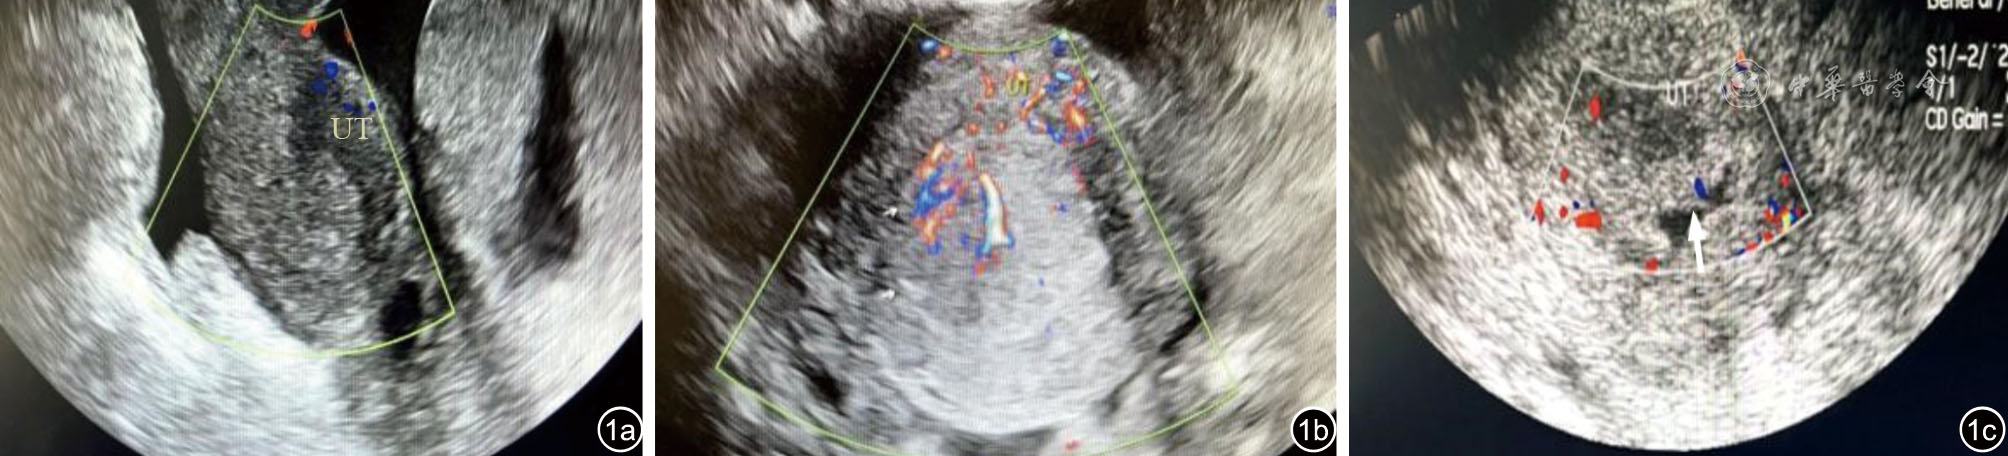

图1 子宫超声声像图表现。图a(例2)患者38岁,子宫内膜样腺癌(高分化),超声显示子宫内膜厚14.2 mm,回声不均匀,与子宫肌层边界清晰;图b(例3)患者44岁,子宫内膜样腺癌(中分化),超声显示宫腔内见25 mm×25 mm×23 mm回声不均区,见分枝状彩色血流信号,与子宫肌层边界清晰;图c(例5)患者59岁,子宫内膜样腺癌(中分化),超声显示宫腔内见17 mm×14 mm×8 mm回声不均区,见点状彩色血流信号,与子宫肌层边界清晰